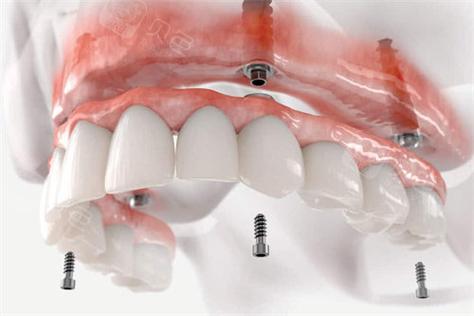

当2颗及以上连续牙齿缺失时,种植桥架可连接多个种植体,形成“种植体-桥架-桥体”的固定修复结构,相较于活动义齿,固定桥桥架无需摘戴,稳定性更高,咀嚼效率接近天然牙,下颌后牙区多颗缺失时,通过植入2-3颗种植体,桥架将种植体连接并延伸至缺失牙位,桥体部分采用高强度材料(如氧化锆)模拟天然牙形态,既恢复牙列连续性,又通过种植体分散咬合力,保护剩余牙槽骨,此类修复避免了活动义齿的基托压迫导致的黏膜不适,且异物感小,患者舒适度显著提升。